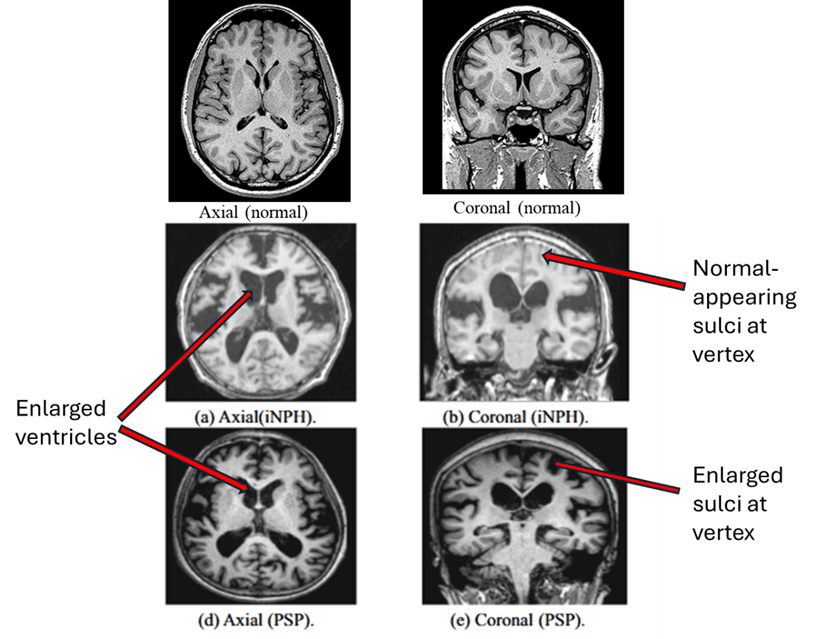

- Insufficient diagnostic value (AUC < 0.900 or sensitivity/specificity ∼80 %) to distinguish PSP from corticobasal degeneration, normal-pressure hydrocephalus, and primary progressive aphasia (a language abnormality that can be caused by multiple specific diseases).